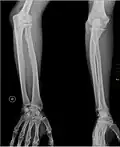

-

Кости предплечья, вид спереди -

Кости предплечья, вид сзади -